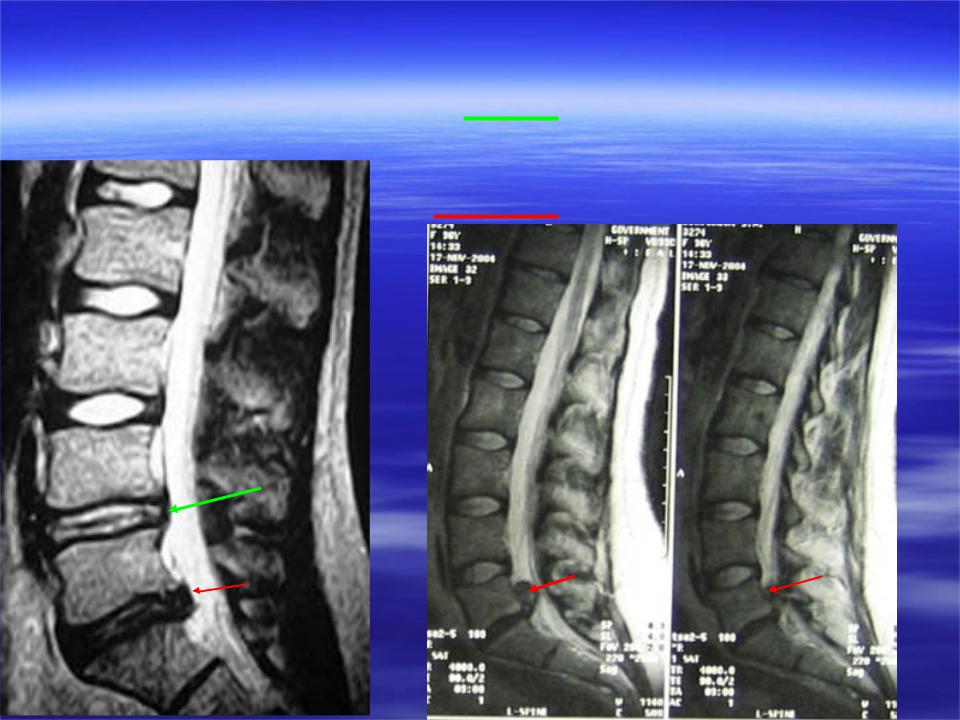

Мрт картина дегенеративно дистрофических изменений пояснично крестцового отдела позвоночника